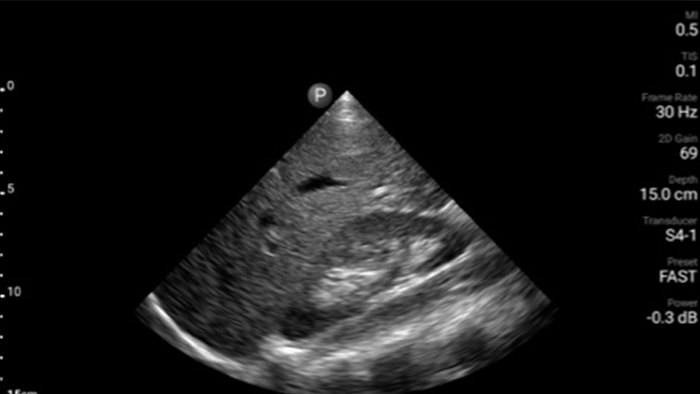

Every second counts in cardiac care

Heart attack patients need immediate care. Lumify's cardiac presets can help patients get diagnosed faster to improve their outcomes.

Lumify S4-1 broadband phased array transducer

• 4 to 1 MHz extended operating frequency range • 2D, color Doppler, M-mode, advanced XRES and multivariate harmonic imaging • High-resolution imaging for abdominal and cardiac applications: Cardiac, OB/GYN, Lung, Abdomen and FAST imaging preset optimizations Lumify aids life-saving technology in prehospital setting

Focused Assessment with Sonography in Trauma (FAST) exam